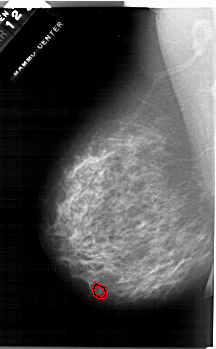

A_1284_1.LEFT_CC

FILE: A_1284_1.LEFT_CC.OVERLAY

TOTAL_ABNORMALITIES 1

ABNORMALITY 1

LESION_TYPE MASS SHAPE OVAL MARGINS OBSCURED

ASSESSMENT 4

SUBTLETY 3

PATHOLOGY BENIGN

TOTAL_OUTLINES 1

BOUNDARY